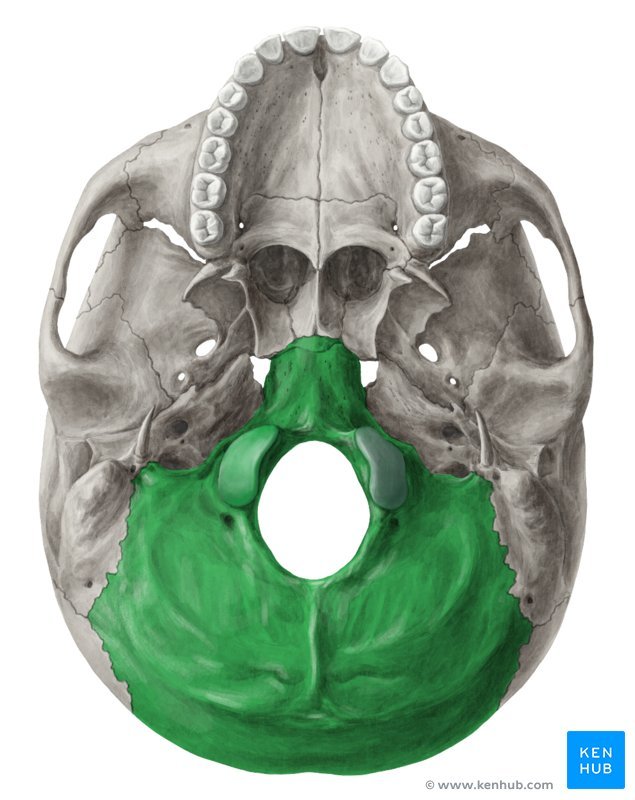

Which bones make up the base of the skull?

What bone is this?

Occipital bone